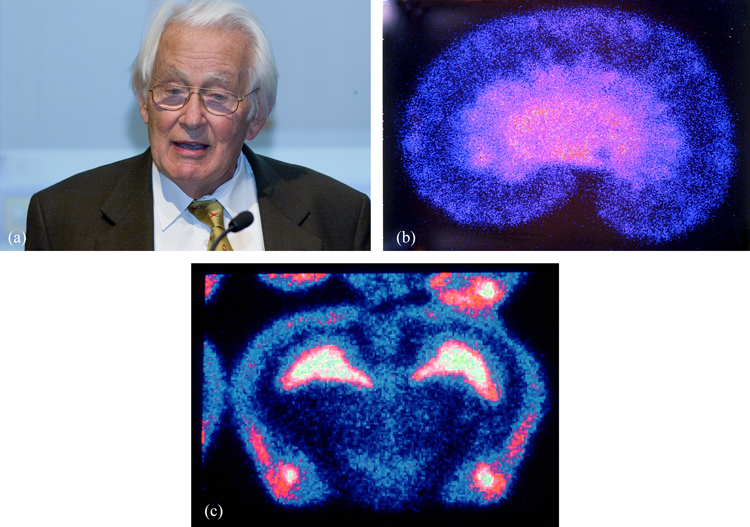

Charpak devoted considerable effort to ensuring that these detectors could be exploited in medical radiology (figure 4). Here the trend is for digital read-out to replace photographic film, since this improves both sensitivity and spatial resolution. Increasing the recording speed also enables faster scanning and lower body doses when using medical diagnostic tools based on radiation or particle beams.

Figure 4. (a) George Charpak invented the multiwire proportional chamber to track particle trajectories, and later applied the same technique to medical imaging. © CERN 2005. These images of (b) a rat kidney and (c) a rat brain were produced using Charpak's multiwire detector, called the parallel plate avalanche chamber (PPAC). © CERN 1993–2017.